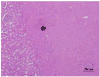

Our recent studies have shown that high-intensity pulsed ultrasound can achieve mechanical tissue fragmentation, a process we call histotripsy. Histotripsy has many medical applications where noninvasive tissue removal or significant tissue disruption is needed (e.g., cancer therapy). The primary aim of this study is to investigate tissue regions treated by histotripsy and to characterize the boundary between the treated and untreated zones using transmission electron microscopy (TEM). The nature of the tissue disruption suggests many clinical applications and provides insights on the physical mechanism of histotripsy. Fresh ex vivo porcine kidney tissues were treated using histotripsy. A 1 MHz 100 mm diameter focused transducer was used to deliver 15 cycle histotripsy pulses at a peak negative pressure of 17 MPa and a pulse repetition frequency (PRF) of 100 Hz. Each lesion was produced by a 3 × 3 (lateral) × 4 (axial) grid with 2 mm between adjacent lateral and 3 mm between axial exposure points using mechanical scanning. Two thousand pulses were applied to each exposure point to achieve tissue fragmentation. After treatment, the tissue was processed and examined using TEM. Extensive fragmentation of the tissues treated with histotripsy was achieved. TEM micrographs of the tissue treated by histotripsy, showing no recognizable cellular features and little recognizable subcellular structures, demonstrates the efficacy of this technique in ablating the targeted tissue regions. A boundary, or transition zone, of a few microns separated the affected and unaffected areas, demonstrating the precision of histotripsy tissue targeting. TEM micrographs of the tissue treated by histotripsy showed no discernable cellular structure within the treated region. Histotripsy can minimize fragmentation of the adjoining nontargeted tissues because, as a nonlinear threshold phenomenon, damage can be highly localized. The potential for high lesion precision is evident in the TEM micrographs.